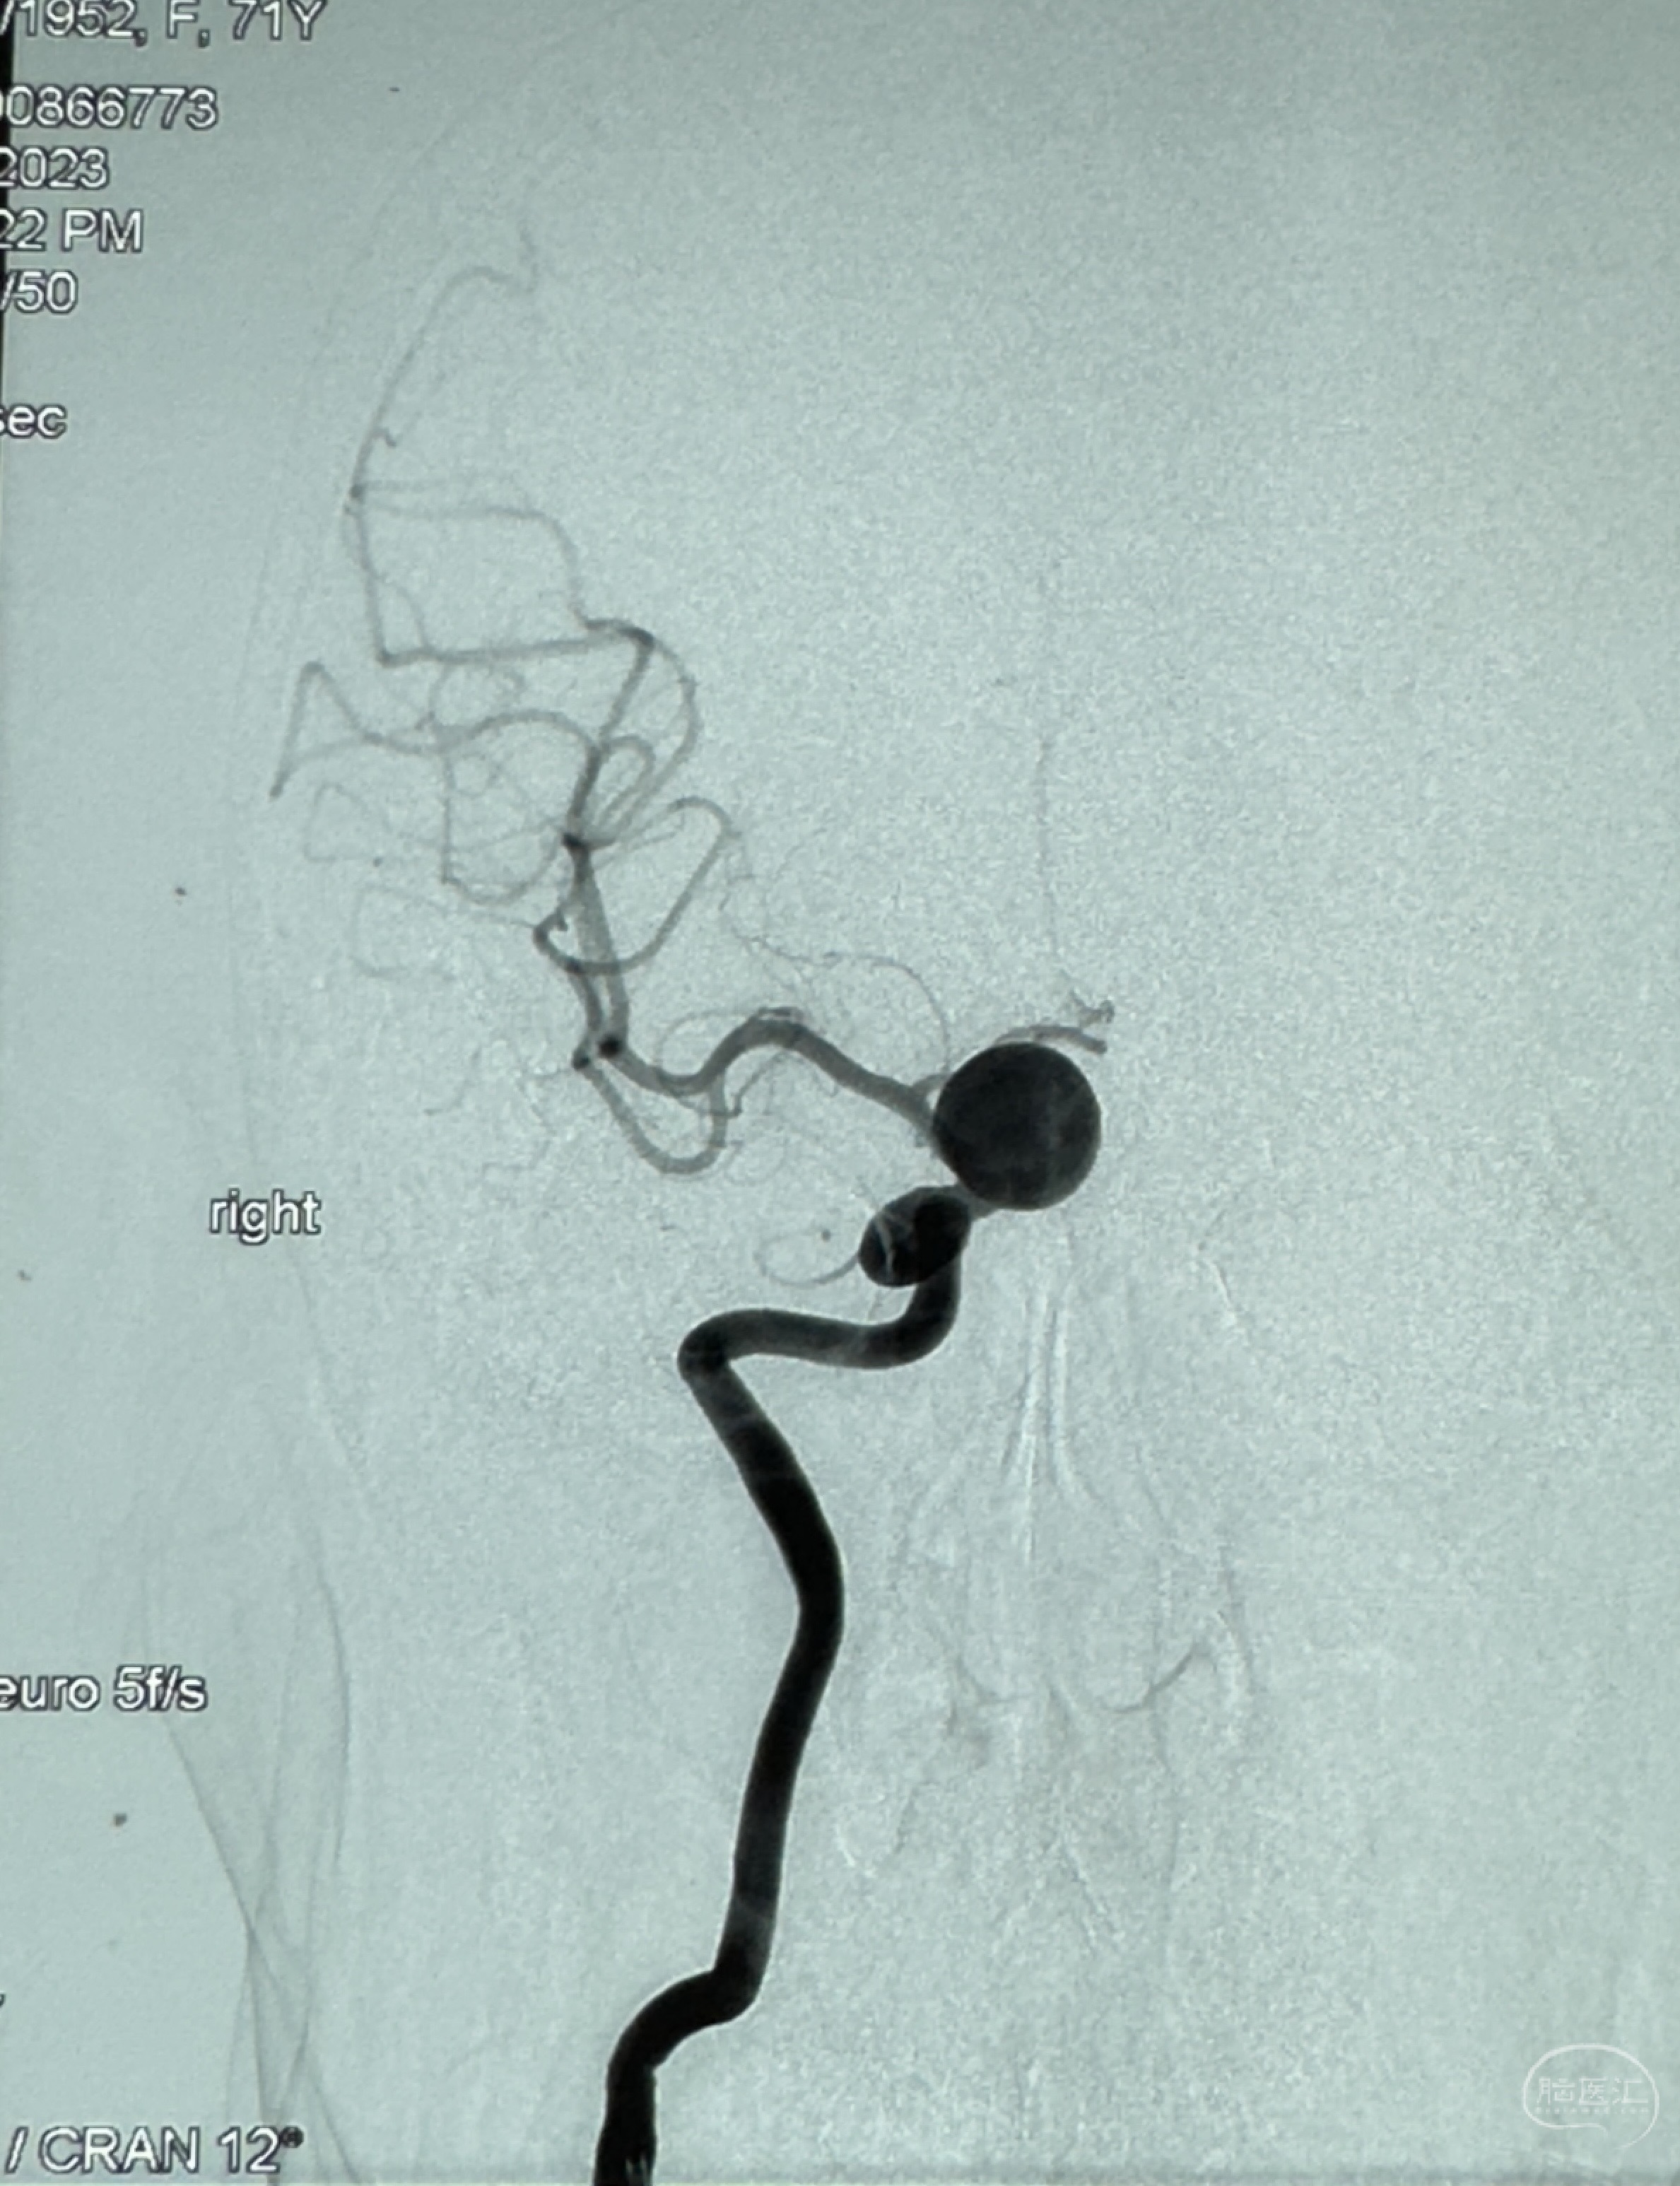

现病史:患者诉2年来反复发作性头痛,顶枕部为主,因自己考虑高血压可能,未予系统检查;患者约20日前无明显诱因下突发剧烈头晕,有天旋地转感,不能睁眼,伴视物模糊;外院查头颅MRI+MRA提示:左侧颈内动脉C6段动脉瘤;遂至复旦大学附属华山医院就诊,于2023-12-08行全脑血管造影提示:右侧颈内动脉C6段动脉瘤,瘤颈6.68mm,动脉瘤大小13.28*12.34mm,建议行密网支架辅助栓塞术治疗,因缺乏相关材料遂出院。现患者仍有顶枕部头痛不适,为求进一步诊疗脑血管病变至我科就诊,收治入院。

2023-12-08 复旦大学附属华山医院 全脑血管造影:右侧颈内动脉C6段动脉瘤,瘤颈6.68mm,动脉瘤大小13.28*12.34mm

2023-12-08外院DSA:右侧颈眼动脉瘤,约13*12mm大小,压颈试验显示左右向及后向前代偿可